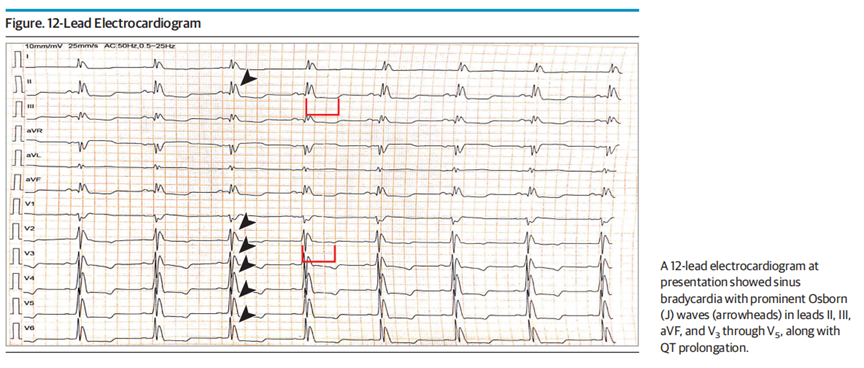

注:入院12导联心电图示窦性心动过缓,Ⅱ、Ⅲ、aVF导联及V3-V5导联明显Osborn波(J 波,箭头标注),伴QT间期延长。

ECG示窦性心动过缓,心室率约40次/分,Ⅰ导联及V2-V6导联QRS波与ST段交界处可见明显Osborn波(J波),其分布范围较文献中典型描述更广。低体温及心动过缓相关的复极延迟共同导致QT间期延长。综合上述ECG表现,窦性心动过缓、QT间期延长与Osborn波高度提示低体温诊断。